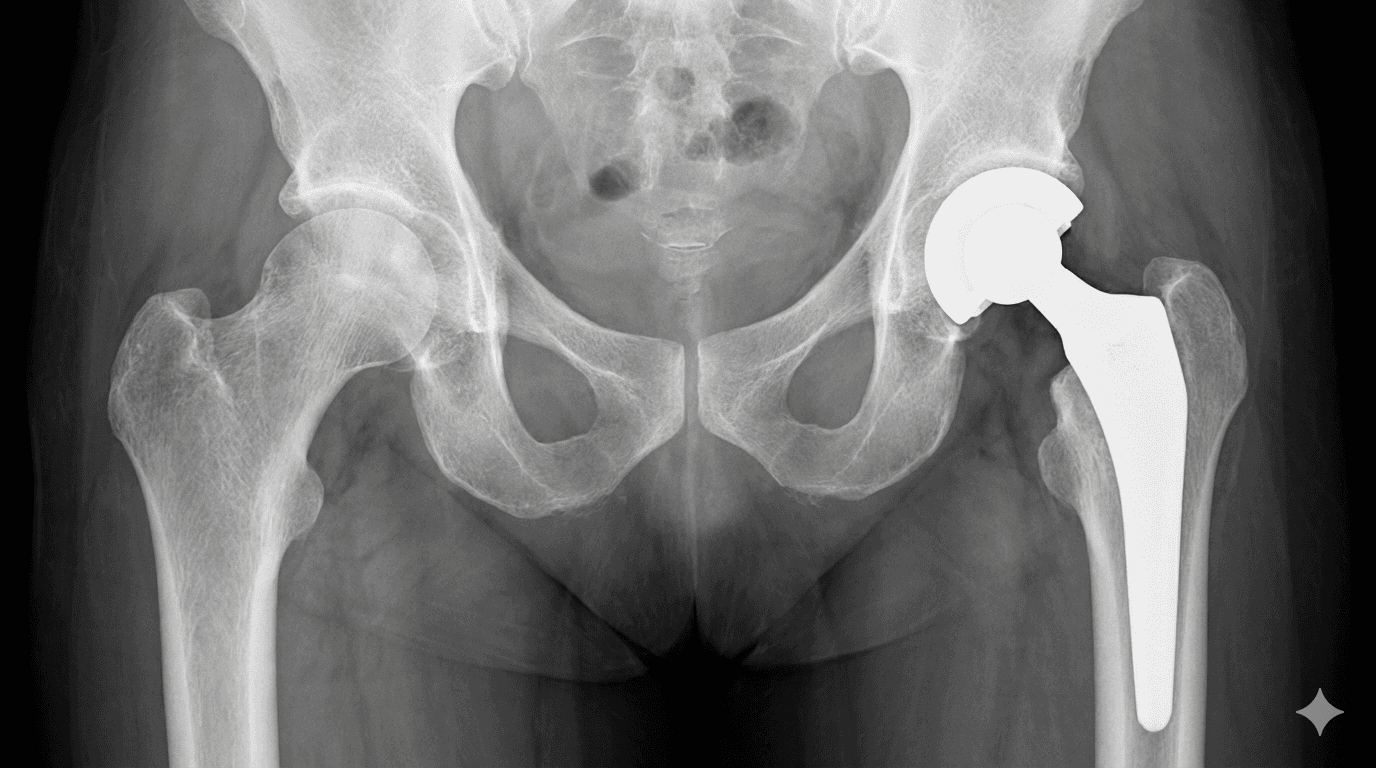

Total Hip Replacement (THR): Performing primary hip replacement surgery in Dubai using modern, durable implants for long-lasting relief from severe arthritis.

Hip Resurfacing: A bone-sparing alternative to total replacement, utilizing techniques offered by experienced hip resurfacing surgeons in Dubai.